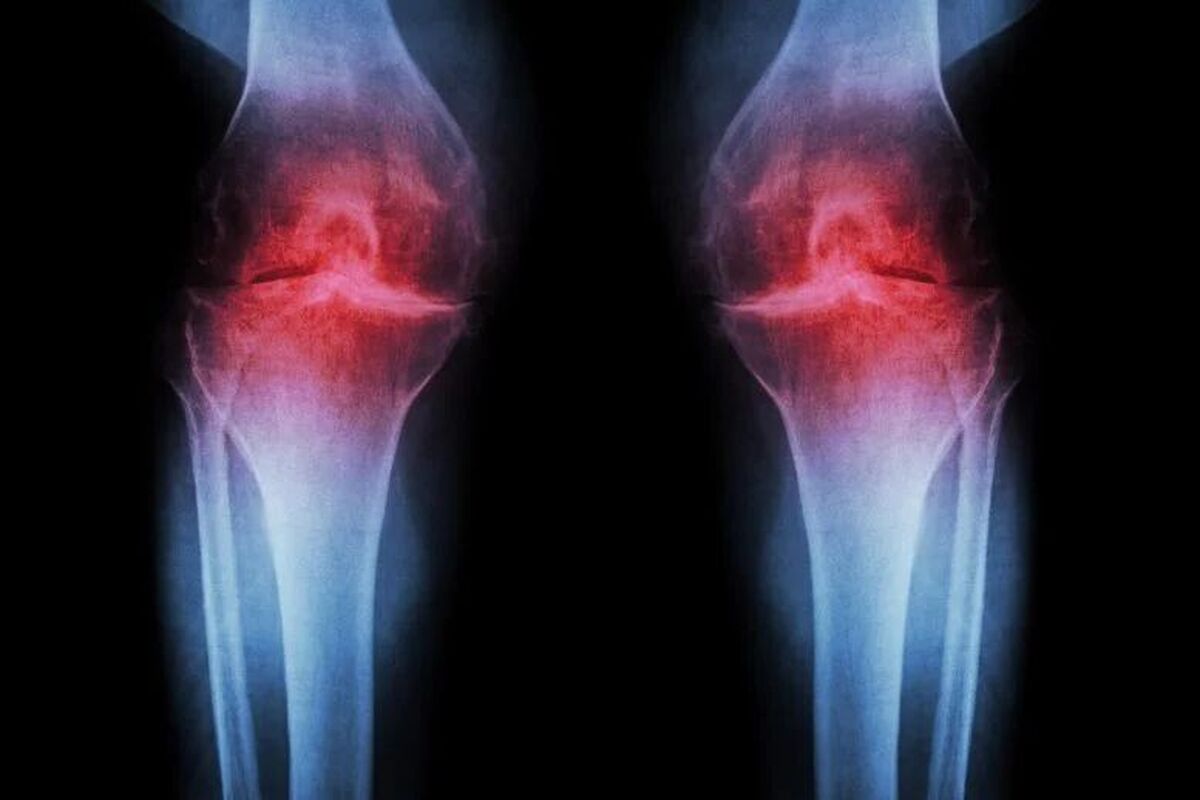

دانشمندان با کشف یک روش درمانی انقلابی اعلام کردند به‌زودی می‌توان غضروف فرسوده زانو را با یک تزریق یا حتی یک قرص بازسازی کرد که از بروز آرتروز پس از آسیب‌های ورزشی مانند پارگی رباط صلیبی جلوگیری می‌کند.

موفق به توسعه یک روش درمانی انقلابی شده‌اند که می‌تواند غضروف فرسوده زانو را بازسازی کند. این درمان با مسدودکردن یک پروتئین پیری خاص، نه تنها غضروف را در موش‌های مسن ترمیم می‌کند، بلکه از بروز آرتروز پس از آسیب‌های جدی مانند پارگی رباط صلیبی (ACL) نیز جلوگیری می‌کند.

بر اساس اعلام پژوهشگران دانشگاه استنفورد، درمان یادشده بر مهار پروتئینی به نام ۱۵-PGDH تمرکز دارد که سطح آن با افزایش سن در بدن بالا می‌رود و نقش کلیدی در تحلیل بافت‌هایی مانند عضلات و غضروف دارد. پژوهشگران با تزریق یک ماده بازدارنده این پروتئین به زانوی موش‌های مسن، شاهد بازسازی چشمگیر غضروف مفصلی از نوع سالم و لغزنده (غضروف هیالین) بودند.

این روش در مدل آسیب‌های ورزشی مشابه پارگی رباط صلیبی نیز موفق عمل و تزریق دارو پس از آسیب، به طور چشمگیری از ایجاد آرتروز جلوگیری کرده است جالب‌تر آنکه بافت غضروف انسانی گرفته‌شده از بیمارانی که عمل تعویض مفصل انجام داده‌اند، در معرض این دارو نیز نشانه‌های واضحی از بازسازی را نشان داد.